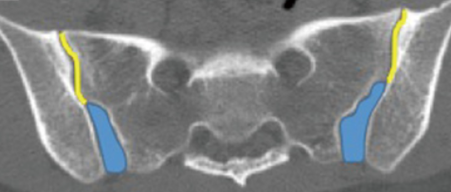

Ostéose iliaque condensante

- Chez la femme post-partums (remaniements de grossesse)

- Zone cartilagineuse

- Triangulaire+++

- Bilatérale